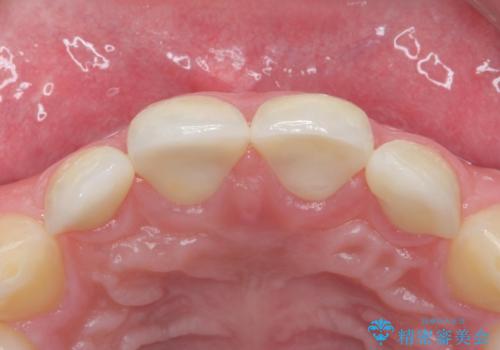

- 右上12左上12 : 仮歯 / 11,000円×4本、ジルコニアクラウン(スペシャル) / 154,000円×4本 合計660,000円(税込)費用は治療当時の料金となります

形のイメージを反映させた仮歯を調整し、技工士さんと連携して製作したため口元に調和した非常に審美的なクラウンを装着することができました。